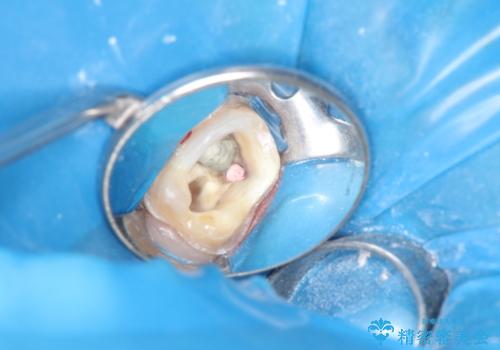

神経の無い歯のクラウン(かぶせ物)は、根管治療を顕微鏡下でしっかりとやり直し、その後に土台の築造とかぶせ物の製作を行うことで今後問題が生じる可能性を可及的に低くできます。

- 神経のある歯を先にセラミック修復し、その後根管治療のやり直しを行う

→最終的にクラウンを製作し、きれいな奥歯を獲得する